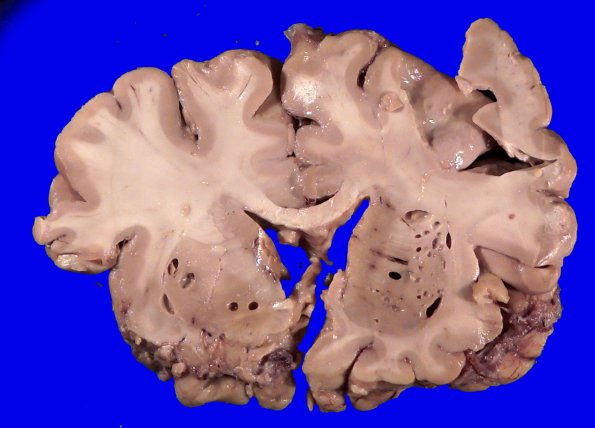

Washington University Experience | BASIC PROCESSES | Artifacts | Artifact - Swiss Cheese Brain | 34A5 Swiss Cheese Brain (Case 12) Gross _5

Gray matter is not spared. In the basal ganglia some of the cystic expansions follow the lenticulostriate penetrating vasculature and smaller vessels.